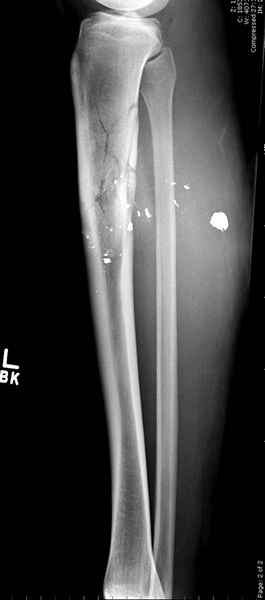

1 неполный перелом большеберцовой кости перкутанная пластина

2 перелом бедра

3 такие раны после удаления пули и остатков одежды можно закрыть первично

Имя     : 1 GSW tibia.jpg

Тип     : image/jpeg

Размер  : 16233 байтов

Описание: отсутствует

Url     : http://weborto.net:8080/pipermail/ortho/attachments/20090726/b21ae3ea/attachment-0011.jpg